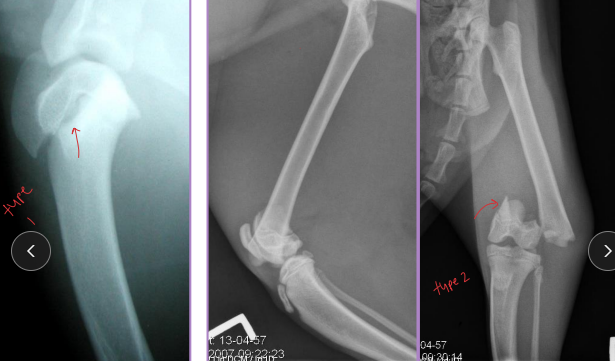

Types of External Skeletal Fixation

Types:

Linear: Frame strength ↑ with complexity

Type IA: Unilateral, uniplanar

Type IB: Unilateral, biplanar

Type II: Bilateral, uniplanar

Type III: Bilateral, biplanar

Linear Type 1/A ESF

½ pins

Unilateral, uniplanar

all pins enter one 1 side

all pins going in the same plane (medial→lateral)

Linear type 1B ESF

Unilateral, biplanar

different planes

Linear type 2 ESF

Full pins

Bilateral, uniplanar

same plane (medial → lateral)

Linear type 3 ESF

full pins and ½ pins

bilateral, biplanar

type 1+2

Frame strength increases as frame complexity increases